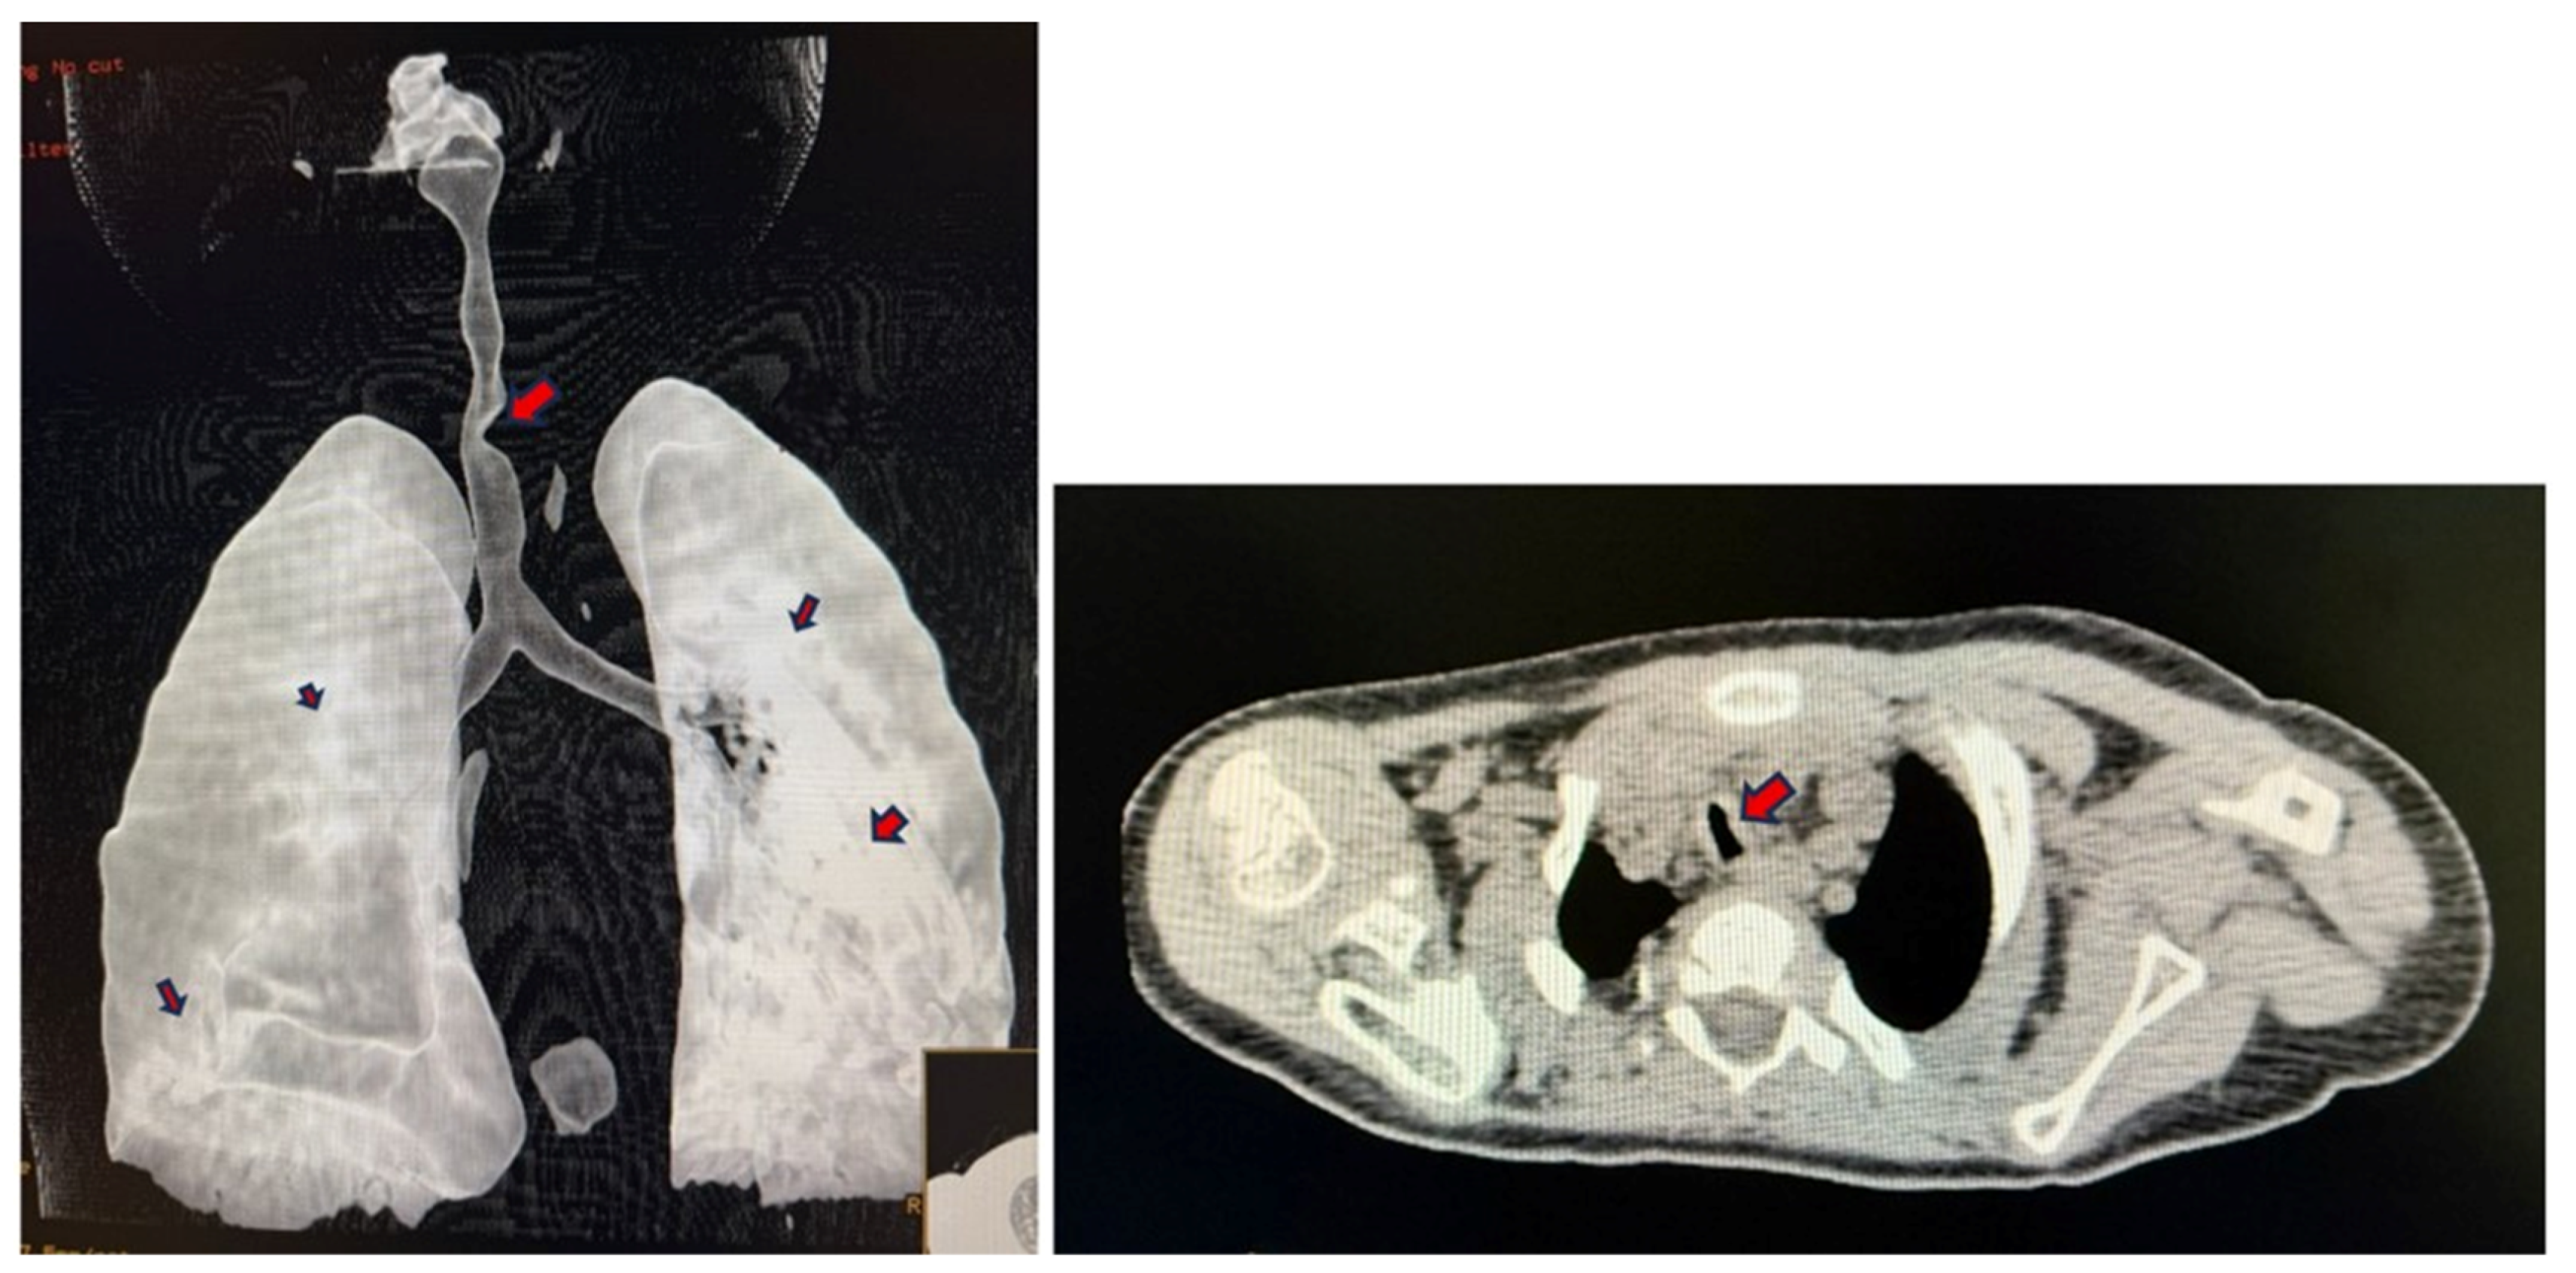

2. Ethical Issues

3. Case Presentation

4. Discussion